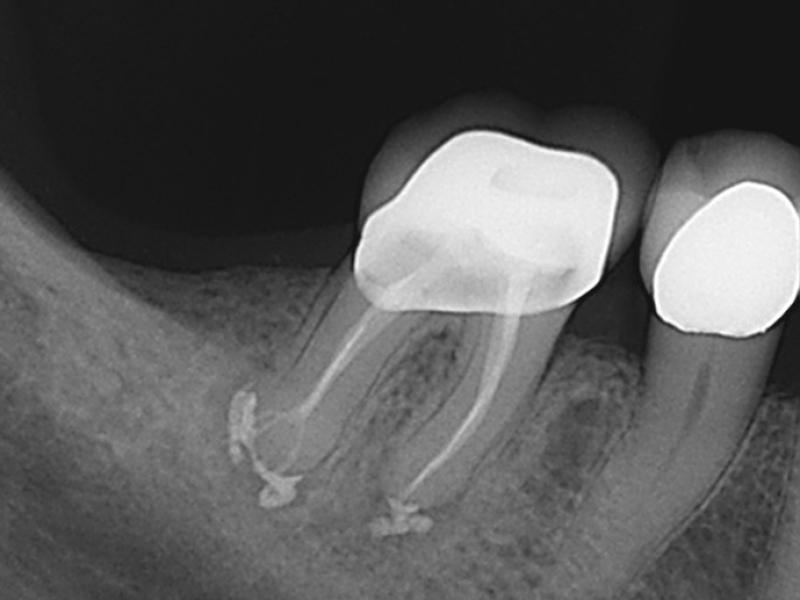

Post-Op